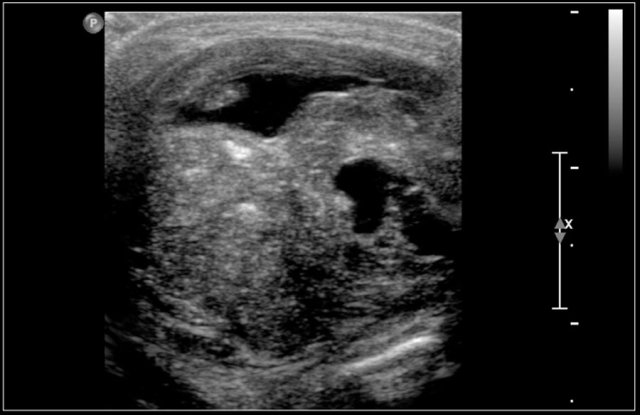

Here another fourteen-year-old boy with a painless swelling in the left neck.

Ultrasound showed several enlarged lymhnodes.

Continue with the MR and PET/CT...

A coronal STIR image shows the pathologic lymph node masses similar to the PET-CT.

The diagnosis was Hodgkin's lymphoma.